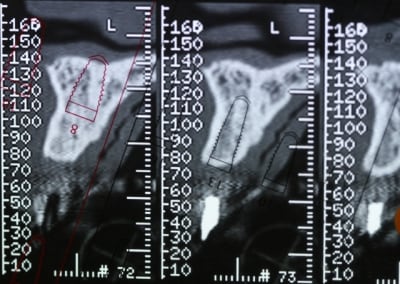

Bon voila le scann de 11-12 (pas 21-22 comme noté)

C'est vrai que j'ai à mort d'os en épaisseur.

Le manque est surtout en hauteur.

Dans tous les cas je refais 21 en même temps.

Tu ne ferais qu'un conjonctif enfoui ? Tu crois que c'est fiable dans le temps ?

et une petite distraction verticale pour gagner 4 à 5 mm en hauteur et les tissus mous en prime?

tu exagères, 4-5 mm en hauteur pour quoi faire pxav ?

j'ai l'impression qu'il ne manque pas d'os en verticale, ou à peine en 12.

Un bon cj avec un lambeau décalé en palatin ou en rouleau pour gagner en épaisseur me semblerai suffisant

le montage guide RX laisse supposer un manque d'un mm en 12 et ok en 11. Surcomble en cj pour en éliminer au cas où avant les empreintes